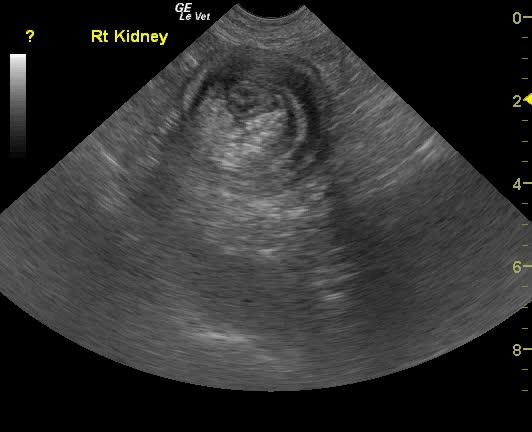

Ileocecocolic intussusception. Moderate chronic renal disease.